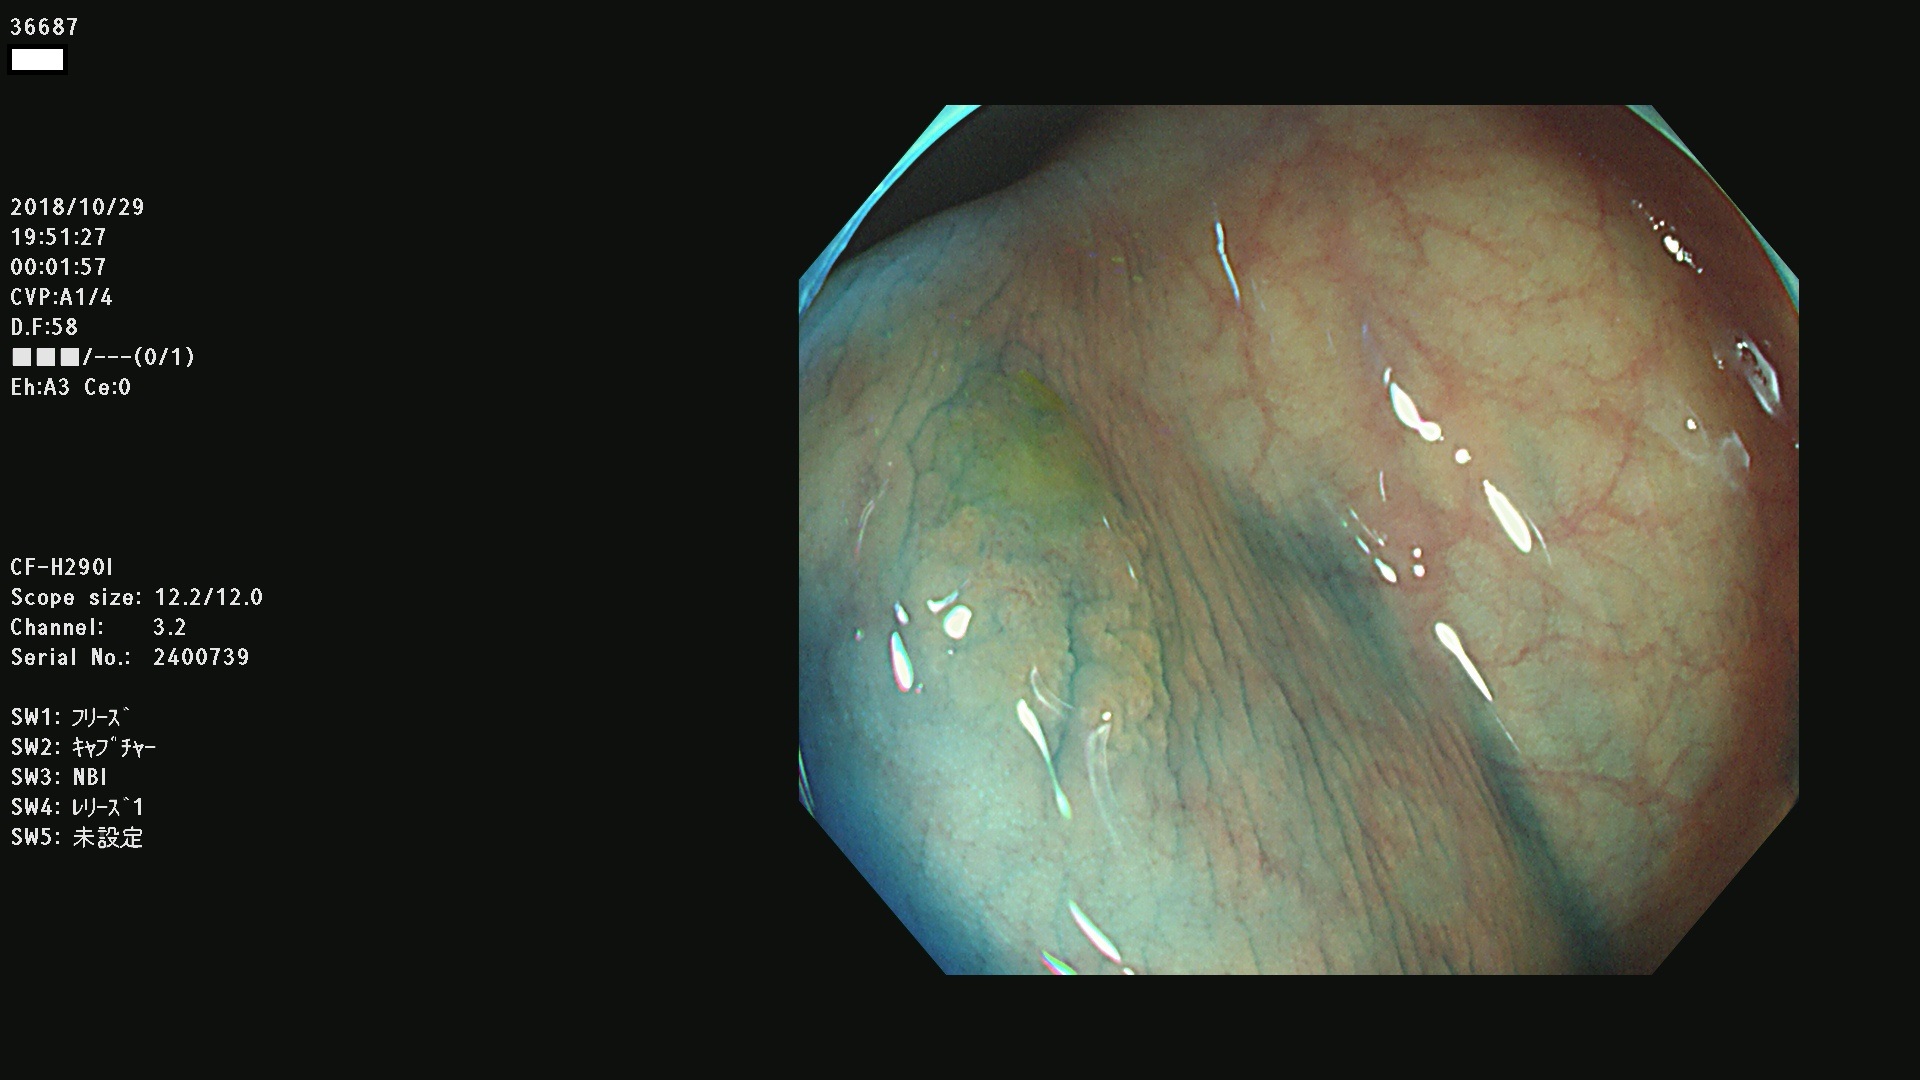

36600 36601 36603 36605 36606 36608 36609 36610 36611 36612 36613 36615 36617 36620 36621 36624 36625 36626 36627 36628 36629 36631(SSAPのみ) 36632 36633 36634 36636(SSAPのみ) 36637(SSAPのみ) 36639 36640 36642 36643 36644 36646 36647 36648 36649(SSAPのみ) 36650(SSAPのみ) 36652 36653 36654 36655(SSAPのみ) 36656 36657 36658 36659 36660 36661(SSAPのみ) 36665 36668 36669 36672 36673 36676 36677 36678 36679 36681 36682 36683 36684 36685 36687(SSAPのみ) 36691 36692 36693 36694 36695 36696 36697 36699(SSAPのみ)

発見困難で危険性の高い平坦型病変(上記100名より抽出)